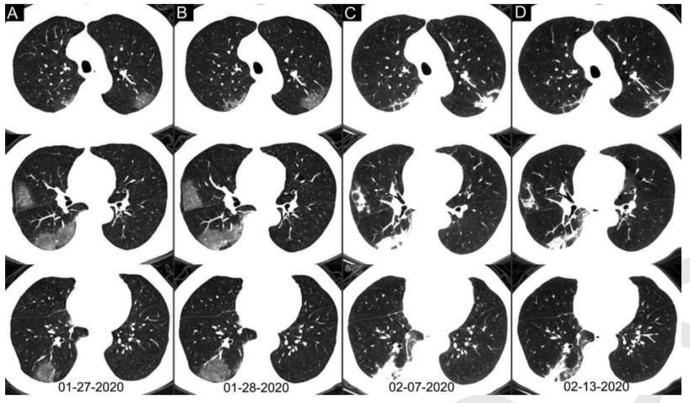

早期出现小斑片或间质性改变,常有磨玻璃阴影;

病灶主要位于胸膜下。随着病情进展,病灶常为双肺多发。

随着病情进展,CT失去特异性,不容易鉴别与一般的肺炎。

60~93%的病例在初始核酸检测阳性之前(或同时)具有与新冠肺炎一致的初始CT阳性表现。42%(24/57)的病例在核酸检测结果转为阴性之前,其胸部CT扫描已经显示病灶吸收。